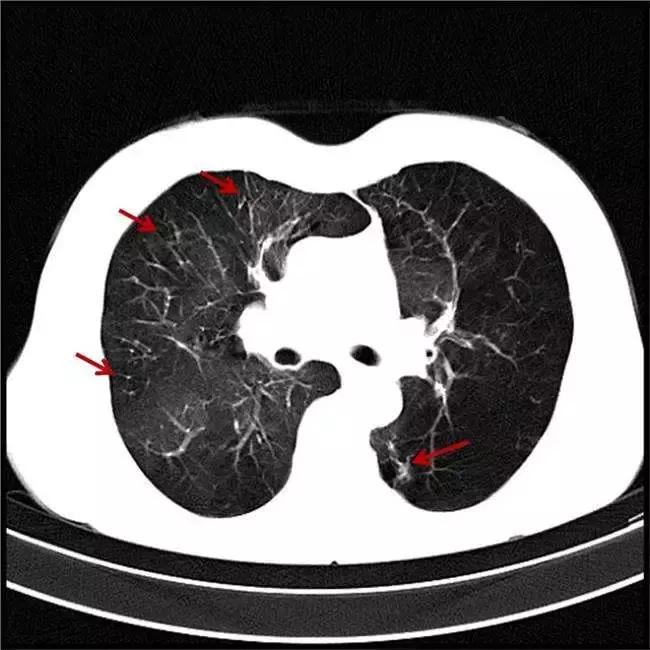

肺纹理增多(或者是增重/增加/增强)

肺纹理由肺动脉、肺静脉、支气管、神经、淋巴管等结构组成。造成肺纹理增多的常见原因有:

▶ 支气管性纹理增强——常见于支气管炎

▶ 血管性纹理增强——常见于心脏病变引起肺血改变

▶ 淋巴性纹理增强——常见于淋巴管炎、淋巴管转移

▶ 生理性肺纹理增多——常见于老年人和肥胖者

总的来说肺纹理增多这个诊断主观性较强。导致肺纹理增多的原因也有很多种,有病理性的,也有生理性或技术性的。孤立地报告肺纹理增多,临床价值不大。只有认真的分析肺纹理增多的具体性质和原因,并且与其他影像学特征、临床病史及技术条件结合起来综合考虑,才能得出正确的结论。

Fig 1 肺纹理增多(箭头所示)